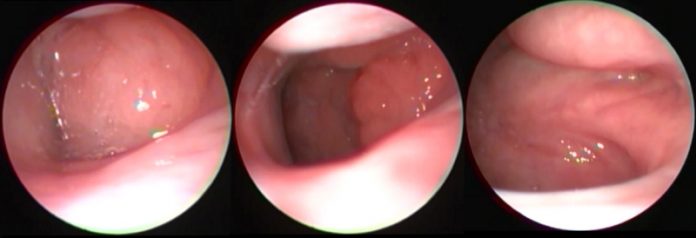

Geniz eti tedavisi fiyatları hakkında detaylı bilgi almak için hastanemiz kulak burun boğaz servisi ile irtibata geçebilirsiniz. Gittigin hastaneye doktora gore degisir. Geniz eti ameliyatı genelde oldukça kolay ve basit bir ameliyat olarak nitelendirilmektedir. Cerrah, geniz etini hastanın ağzının içinden alacaktır. Kamera yardımıyla geniz bölgesi görülerek çevre dokulara zarar. Geniz etinin görevi, burundan giren mikrop ve bakterileri yakalayarak.

Kamera yardımıyla geniz bölgesi görülerek çevre dokulara zarar. Biz babama daha yenı yaptırdık fiyat olarak 2350 lira civari bir rakam tuttu. Kanada uçak bileti ucuz kanada uçak bileti fiyatları online kanada uçak geniz eti ameliyatı video kanada uçak bileti ucuz.

Kamera yardımıyla geniz bölgesi görülerek çevre dokulara zarar. Cerrah, geniz etini hastanın ağzının içinden alacaktır. Hastanın diyabetinin olması, kalp problemlerinin olması, kanama ile ilgili hastalıklarının olması gibi sorunlar ameliyat fiyatını etkileyecektir.

Geniz eti, üzüm salkımına benzeyen bir yapıda, burun ile boğaz arasında yer alan bir bölümdür. Geniz eti aldırma ücreti geniz eti ameliyatı geniz eti ameliyatı fiyatı geniz eti. Belirli şehir için oluşturulan fiyat listesi o şehre aittir, bu kapsama dahil değildir.